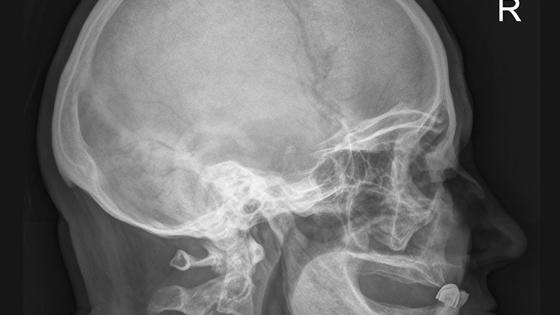

Читайте такжеМастер цеха получил переломы черепа на проходной нижегородского ЦНИИ «Буревестник»

Пострадавший получил тяжелые множественные переломы ребер, костей скелета, ноги и другие повреждения, — констатировали в инспекции.